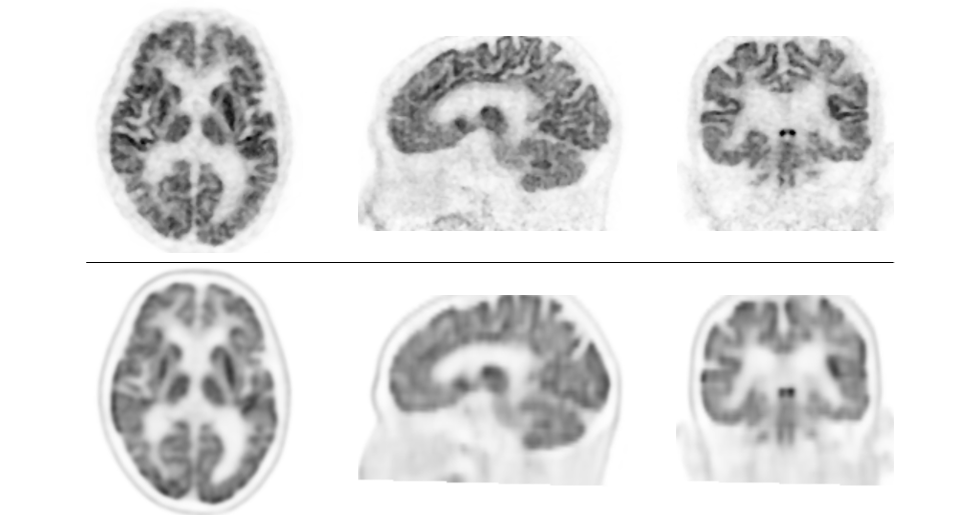

高分解能PET装置で従来よりも高画質な画像を撮像 正確な診断が可能となり、認知症の早期治療への貢献に期待